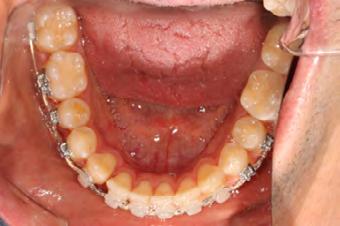

Approximately six months after insertion of the RPE, digital scans were taken for SureSmile custom wires and the patient was scheduled for the SFOT procedure with the oral surgeon. The RPE was removed, SureSmile wires inserted and segmental corticotomies performed, immediately followed by further vertical elastics on the right side (Figure

4). Archwires were upgraded incrementally into 19 x 25 SS. Once the bite was completely closed, the patient was referred to the myofunctional therapist to begin treatment. Eight sessions of myofunctional exercises were performed, focusing on muscle building, toning, synchronicity and awareness. Improvement in correct chewing, swallowing and resting postures of the lip and tongue were addressed. All appliances were removed 21 months after initial insertion (Figure 5), and the patient was referred to a re-

Figure 4. Post-corticotomy, with SureSmile custom wires.